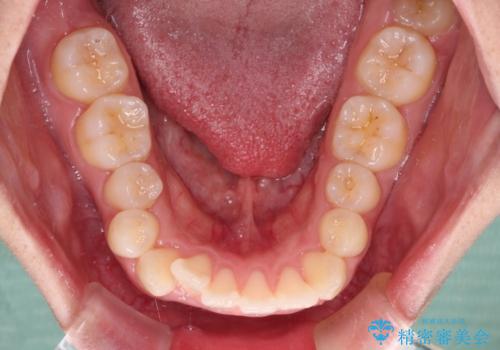

4本の歯を抜歯したことで、飛び出していた口元が引っ込み、横顔の印象が大きく改善されました。